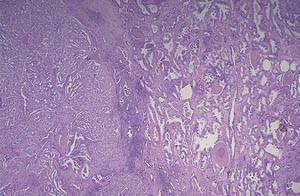

Патологоанатомическая классификация.

Криброзная аденокарцинома предстательной железы.